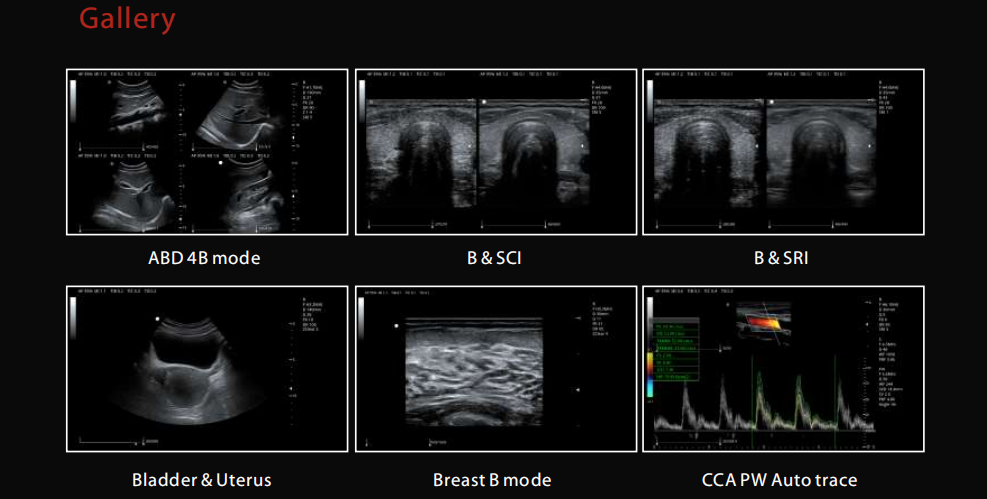

2D, CFM, M, PW, CW, CMM, DPDI, AMM, 3D/4D, ZPage, ZLive, TDI, elastography, panoramic imaging |

THI, SRI, SCI, TSI, FCI, EFOV, HR Flow, B Steering |

Standard automatic IMT measurement |

Support PW automatic tracking and automatic calculation |